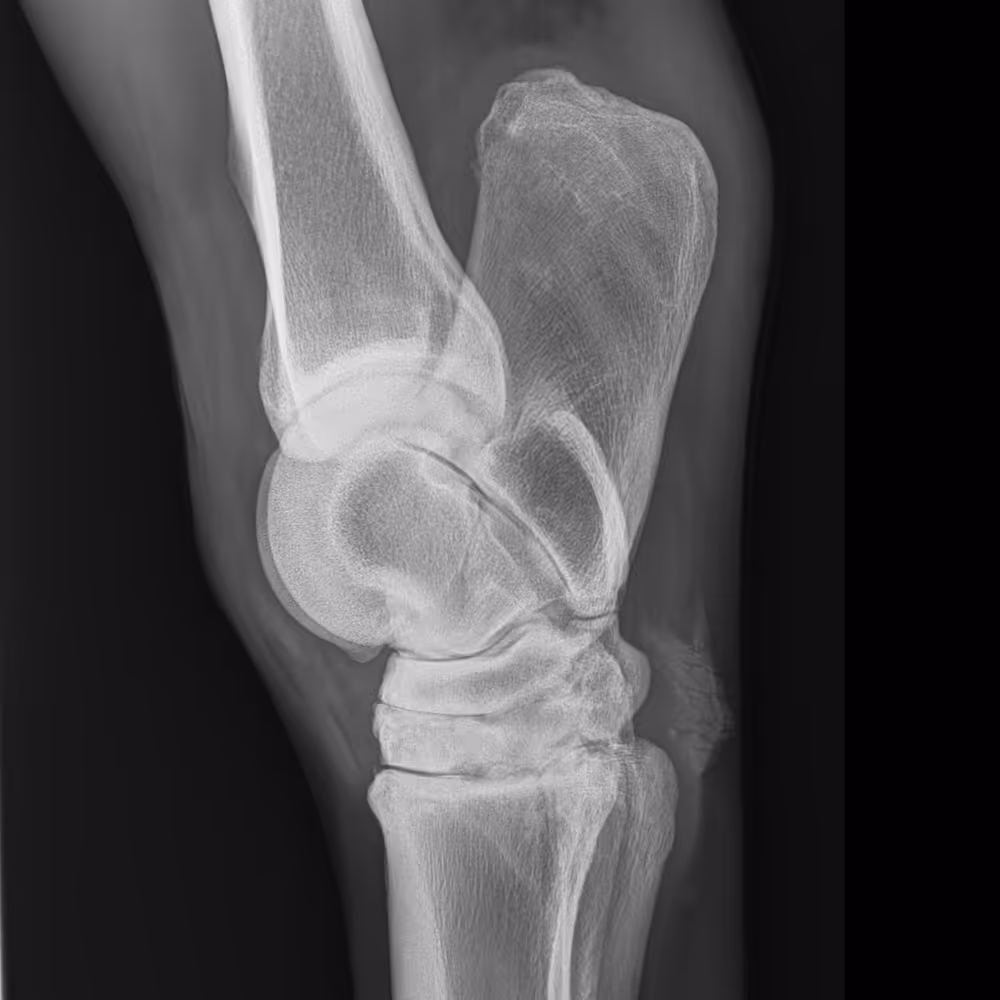

X-ray image

Severe OA of the elbow, with obvious new bone formation medially and cranially, subchondral bone density changes, and a narrowed joint space medially.